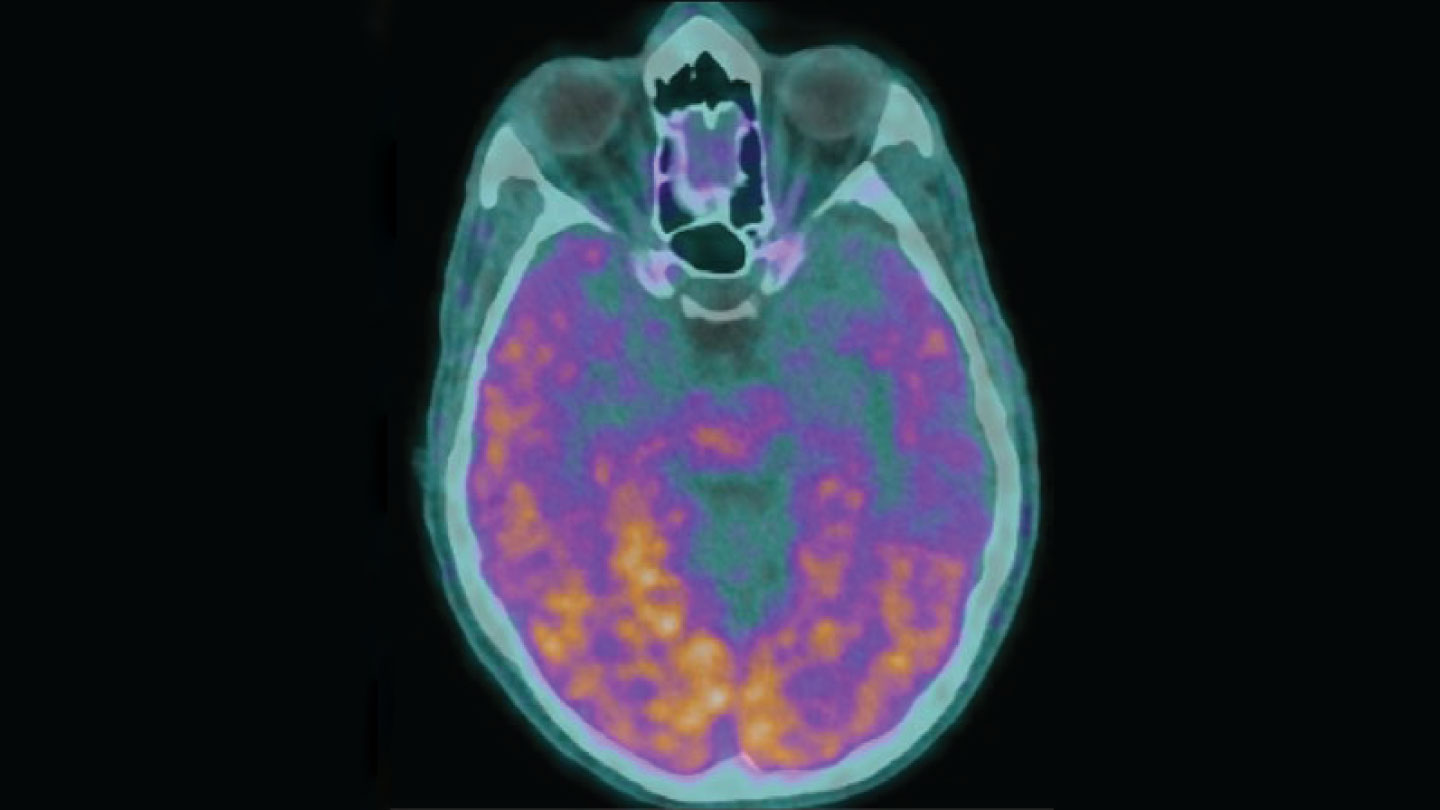

Transmissible Alzheimer’s?

Alzheimer’s disease is not contagious in everyday life, but under extremely rare conditions, it may spread from one person to another (SN: 2/24/24, p. 6). Five people who in childhood received contaminated growth hormone injections later developed early-onset Alzheimer’s — most likely because the hormones were tainted with amyloid-beta, a protein whose buildup is linked to the disease, researchers say. But it’s not yet clear whether the growth hormones are to blame, other experts note. Perhaps the health conditions that those hormones were meant to treat or other medical procedures led to the development of Alzheimer’s in these patients.